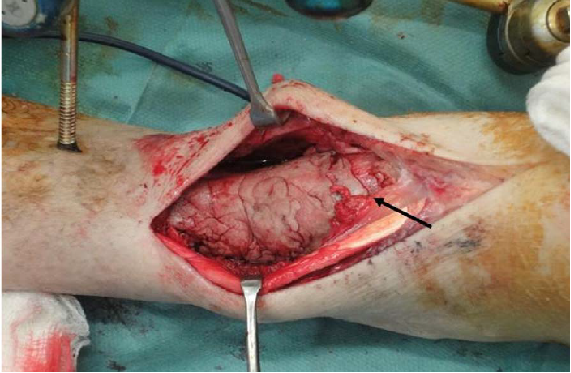

(三)诱导膜

诱导膜紧贴在骨水泥表面,肌肉组织以下,其作用在于机械包裹松质骨,隔离软组织并提供丰富的血供。术中应全层切开,避免过多分离诱导膜上方的肌肉及皮下组织,减少对其血供的损害(图4)。因此,诱导膜内丰富的血管和其完整性均非常重要[31]。为了减少骨不连的发生,诱导膜通常需要超过骨折端2 cm以上。一期清创术后骨折端需使用骨刀磨除骨皮质,并用骨水泥包裹。感染性骨缺损清创术后通常使用外固定架固定,但外固定架易松动可能会影响骨移植区诱导膜的血供。Yu等[32]报告清创术后采用抗生素骨水泥被覆钢板固定,可达到坚强固定与控制感染的目的。二期手术去除骨水泥时,应注意保护诱导膜的完整性,避免过度牵拉和使用过氧化氢清洗伤口;内固定钢板尽可能置于诱导膜外,以减少其产生的遮挡效应,通常采用的方法是在切口的前方或后方置入钢板(图5),以减少钢板下方的骨吸收。由于移植骨在获得影像学骨愈合后仍然还有较长的皮质化塑形期[33],所以长期使用外固定架固定易出现钉道感染和外固定架松动,不利于移植骨的塑形[34]。Wang等[35]和Luo等[36]在二期重建时均主张使用内固定。抗生素涂层髓内钉在局部释放抗生素杀灭细菌,同时能减少植骨量和维持肢体的长度[37]。

图4 术中应全层切开,避免过多分离诱导膜上方的肌肉及皮下组织,减少对其血供的损害